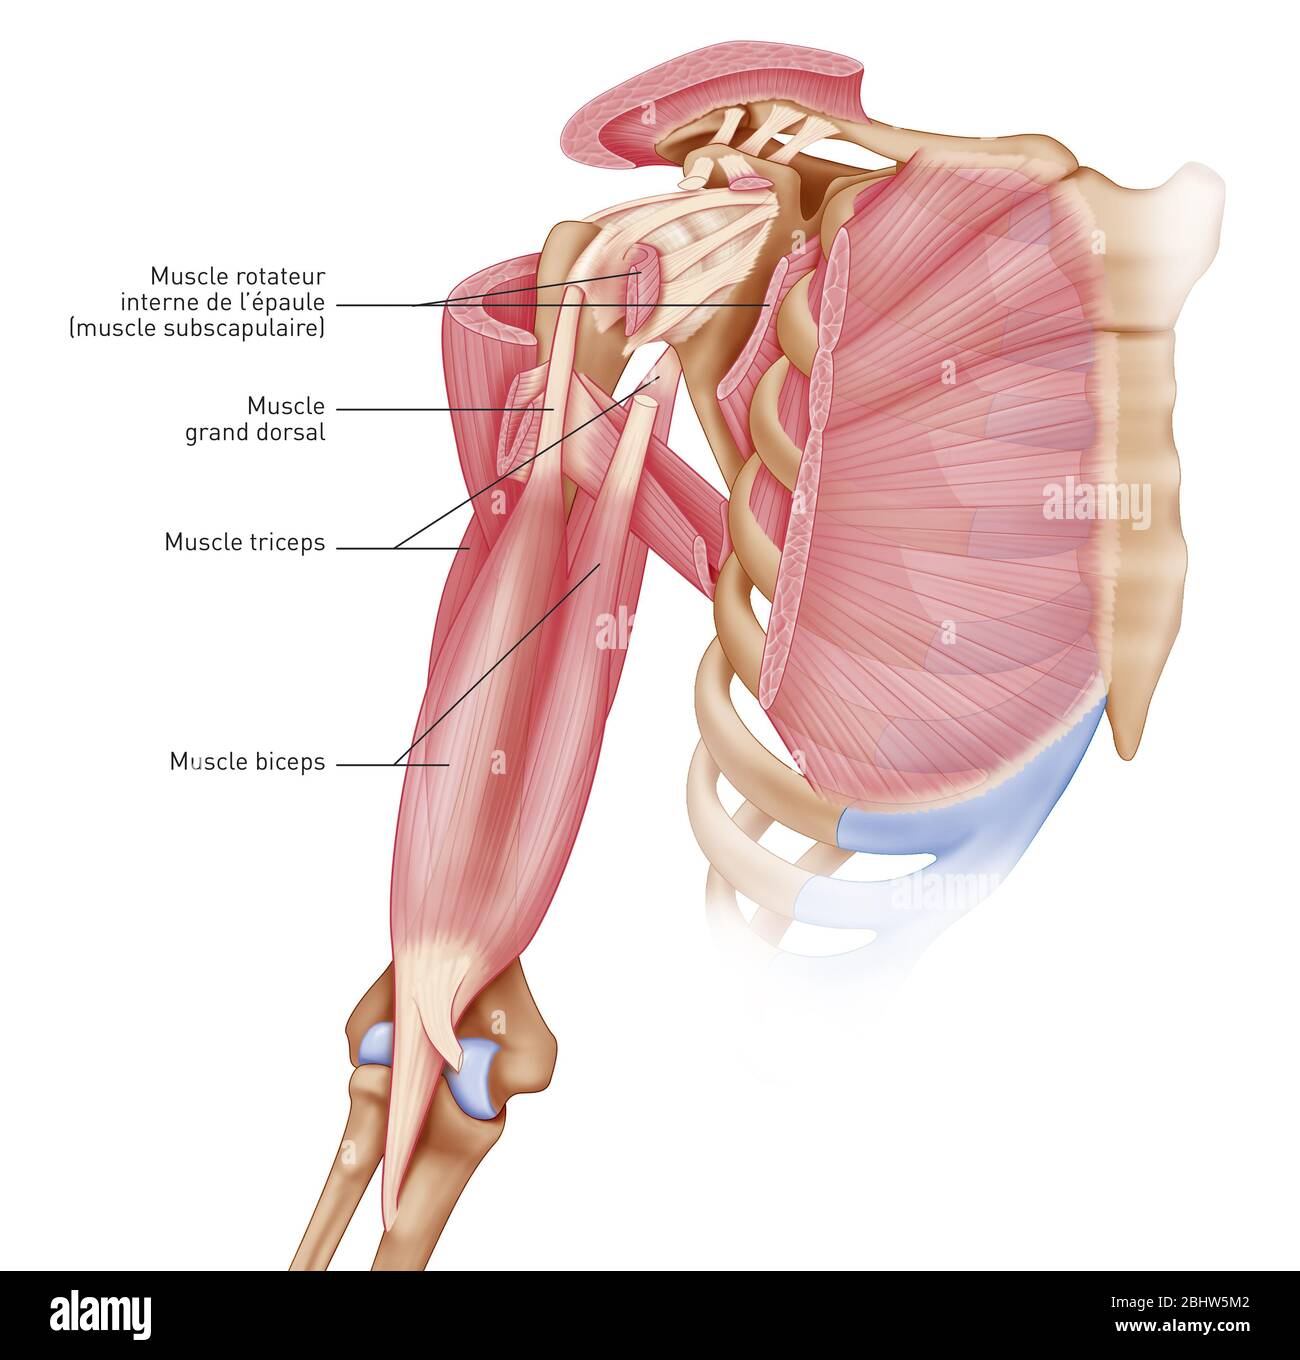

Medical illustration representing pathologies of the shoulder. The articular capsule, the ligaments, the small pectoralis and coraco-brachial tendons Stock Photohttps://www.alamy.com/image-license-details/?v=1https://www.alamy.com/medical-illustration-representing-pathologies-of-the-shoulder-the-articular-capsule-the-ligaments-the-small-pectoralis-and-coraco-brachial-tendons-image355209807.html

Medical illustration representing pathologies of the shoulder. The articular capsule, the ligaments, the small pectoralis and coraco-brachial tendons Stock Photohttps://www.alamy.com/image-license-details/?v=1https://www.alamy.com/medical-illustration-representing-pathologies-of-the-shoulder-the-articular-capsule-the-ligaments-the-small-pectoralis-and-coraco-brachial-tendons-image355209807.htmlRM2BHW5MF–Medical illustration representing pathologies of the shoulder. The articular capsule, the ligaments, the small pectoralis and coraco-brachial tendons

Medical illustration representing the muscles of the shoulder, joint and shoulder muscles. The articular capsule, the ligaments, the small pectoralis Stock Photohttps://www.alamy.com/image-license-details/?v=1https://www.alamy.com/medical-illustration-representing-the-muscles-of-the-shoulder-joint-and-shoulder-muscles-the-articular-capsule-the-ligaments-the-small-pectoralis-image355209794.html

Medical illustration representing the muscles of the shoulder, joint and shoulder muscles. The articular capsule, the ligaments, the small pectoralis Stock Photohttps://www.alamy.com/image-license-details/?v=1https://www.alamy.com/medical-illustration-representing-the-muscles-of-the-shoulder-joint-and-shoulder-muscles-the-articular-capsule-the-ligaments-the-small-pectoralis-image355209794.htmlRM2BHW5M2–Medical illustration representing the muscles of the shoulder, joint and shoulder muscles. The articular capsule, the ligaments, the small pectoralis